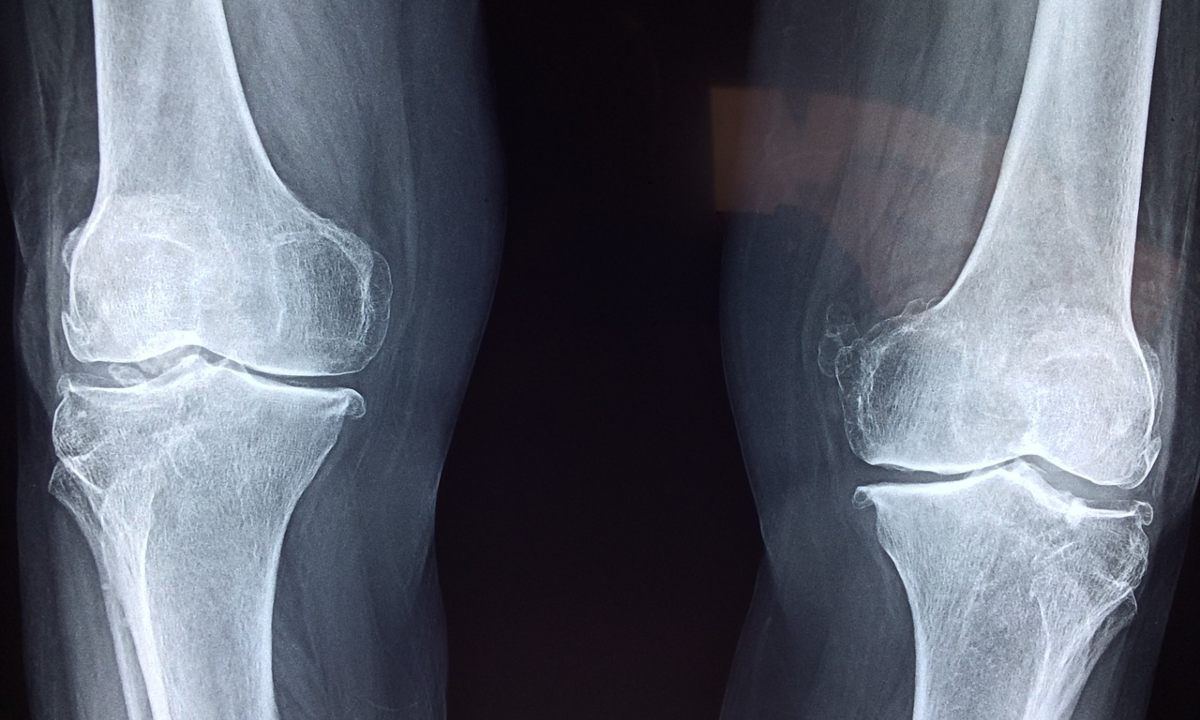

Con el paso del tiempo, los huesos y articulaciones se van desgastando de manera natural. Un claro ejemplo es ese ese dolorcito en la rodilla que a todos nos ha ocurrido alguna vez, sobre todo cuando haces mucho ejercicio o el clima es frío; sin embargo, hay una manera natural de protegerlas antes de llegar a un daño serio y es con el magnesio.

Según una investigación del National Institute of Health, el magnesio interviene en determinadas reacciones químicas para la formación de calcio por lo que uno de los tratamientos más recomendados para la osteoporosis es precisamente este mineral.

Así que, ya lo sabes, si quieres llegar a tu vejez sin problemas para levantarte del sillón, artritis ni osteoporosis, esta podría ser una buena manera de prevenir.